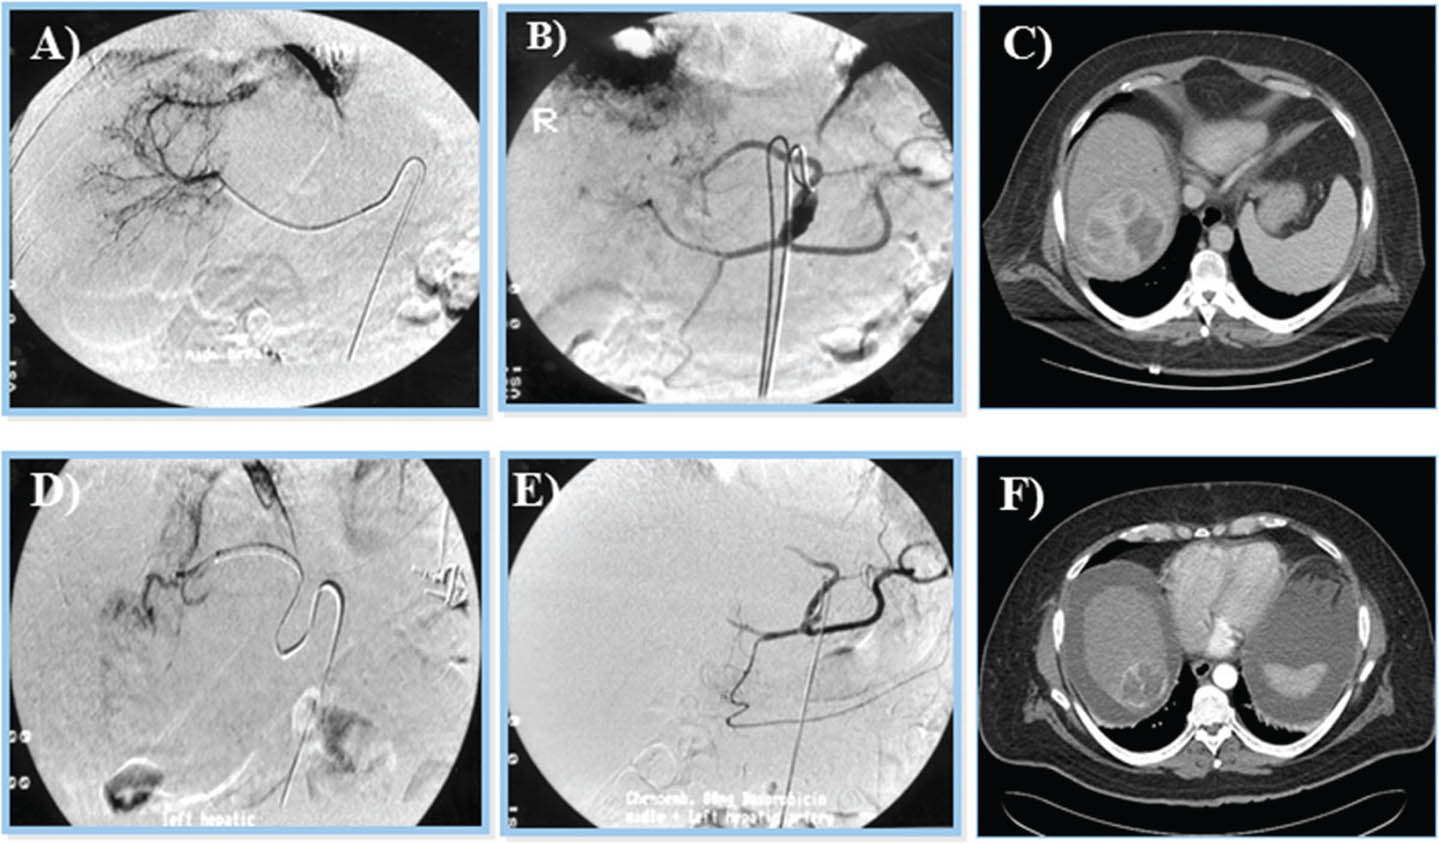

Liver transplantation

Liver transplantation is a curative modality for the patient with HCC and borderline to decompensated cirrhosis (Figure 6) (66). It offers a high survival rate and the lowest probability of tumor recurrence due to the removal of the fibrotic environment (68). Nonetheless, due to the scarcity of graft donors, there is a significant patient mortality from dropping off the liver waiting list due to tumor progression. To overcome longer cadaveric organs offer waiting times, living non- or related-liver transplantation has been presented as an option (66, 68, 69). The ideal candidate for liver transplantation (cadaveric or living-related) are those who satisfy the Milan criteria (solitary tumor up to 5 cm in size, or 3 tumors where the largest tumor is up to 3 cm in size, Figure 7) (66, 70). The Milan criteria showed a low probability of tumor recurrence after transplantation, with over 75% survival in 5 years and over 90% tumor reoccurrence-free survival rate (66, 68). Nevertheless, this concept has been challenged by several groups, and many transplant centers offer liver transplantation for patients with HCC outside of the Milan criteria with acceptable outcomes (66, 71). One other criterion is that of the University of California at San Francisco, which include single tumors ≤6.5 cm or 2 to 3 tumors ≤4.5 cm, with a total tumor diameter ≤8 cm (66, 71).

Fig 6

Figure 6. Liver transplant procedure in a patient with end stage liver disease. A. Liver with advanced fibrosis is removed. B. Replaced with a liver graft form a deceased donor. C. Reperfusion showing satisfactory appeaance. D. Classic vascular and biliary reconstruction performed at the proximal and distal end:end caval anastomosis, porto:portal and common hepatic to common hepatic arterial reconstruction. In this case, no blood products were given to the patient during the procedure. The patient was discharged 6 days after surgery. The patient is alive and doing well 5 years after graft implantation.